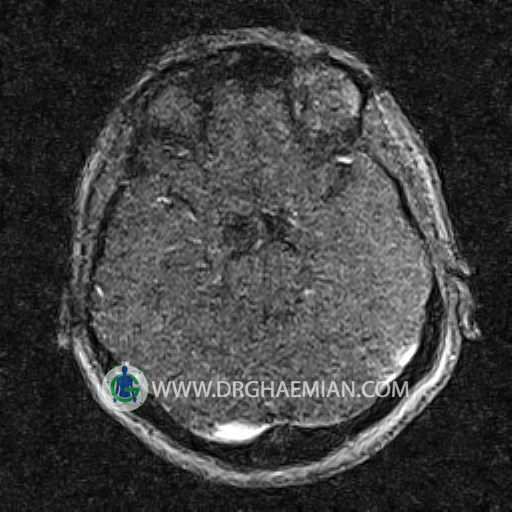

ام آر وی یک روش تصویربرداری دقیق و غیر تهاجمی است که برای معاینه ورید های بدن و ارزیابی سلامت رگ ها استفاده می شود. ورید ها خون را از اعضای بدن به قلب باز می گرداند تا دوباره اکسیژن و مواد مغذی به خون داده شود. ام آر وی جریان خون را ارزیابی و موارد غیرعادی مضر مانند لخته های خونی را شناسایی می کند. در این کیس ترومبوز دیواری مغز در سینوس عرضی راست و ترمبوز جزئی در سینوس عرضی چپ دیده می شود.

(With & Without contrast)

Technique: TOF ( time of flight ).

Images of the venous cranial vessels demonstrates a superior sagittal sinus of normal caliber with normal arrangement of draining superficial cerebral veins.

The great cerebral vein Galen inferior sagittal , straight sinus and left sigmoid sinus appear normal.

The right sigmoid sinus present a normal caliber.

The other evaluable deep cerebral veins , basal and labbe are normally developed and patent.

The other evaluable portions of the neurocranium show no abnormalities.